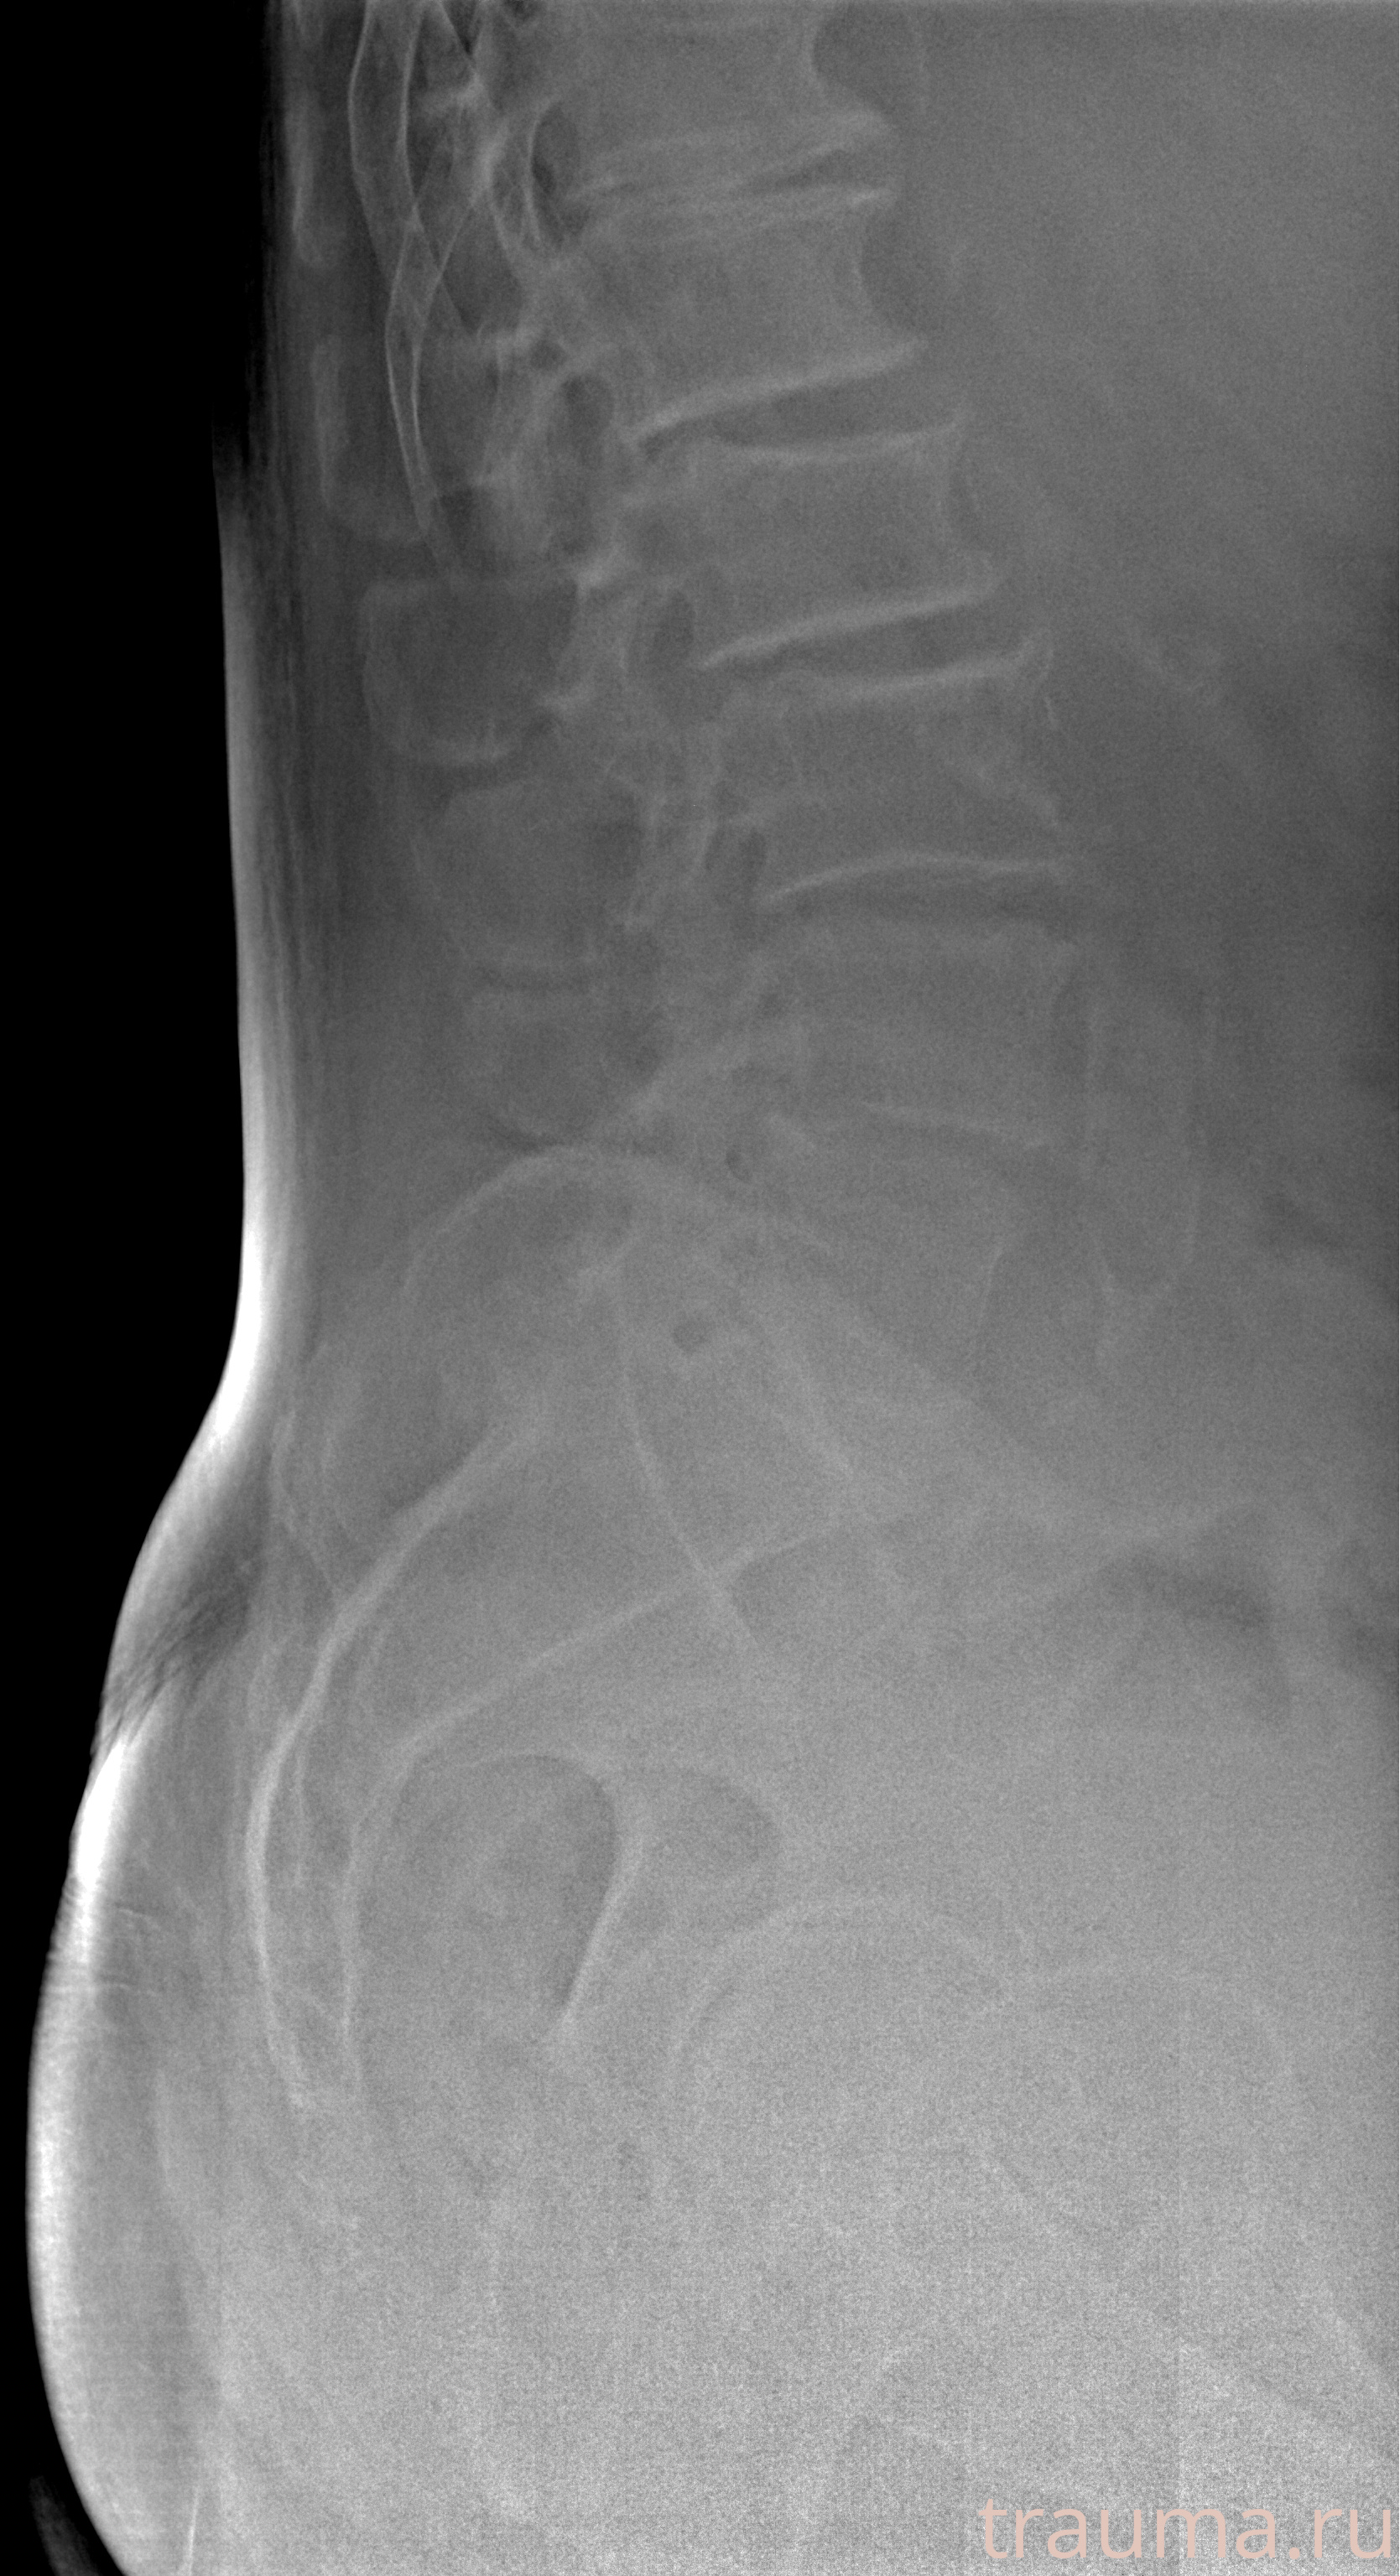

Рентген на дому: по вашему адресу приезжает врач-рентгенолог, травматолог-ортопед с мобильным рентгеновским аппаратом, проводит диагностику травмы или заболевания, делает необходимые рентгенограммы, дает рекомендации по дальнейшему лечению. Получить качественные снимки в домашних условиях возможно благодаря уникальной методике, разработанной МосРентген Центром для института  Склифосовского